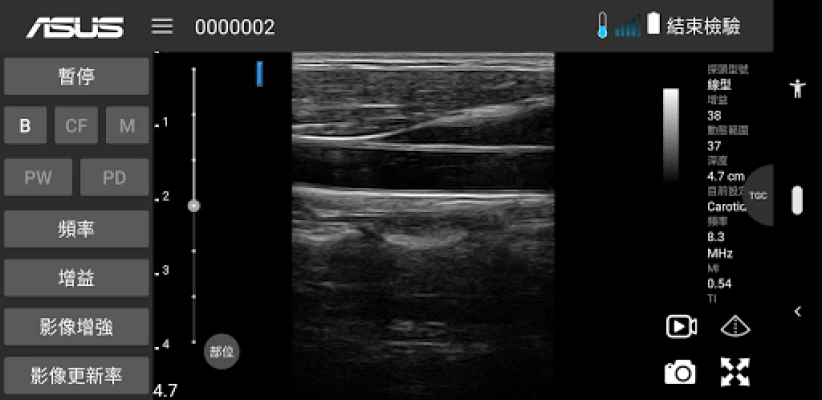

ASUS Portable Ultrasound is a wireless, handheld, pocket-sized imaging tool.

This flexible and feasible APP supports reliable and dependable images for diverse scenarios.